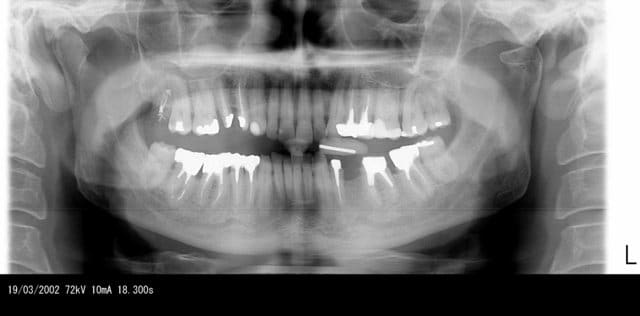

la plupart du temps quand quelqu'un souffre d'une atm, il n'y a rien a la radio panoramique. et encore moins à la tomo et je me demande si parfois on invente un peu

En opposition à ces observations cliniques, le nombre de fois où je découvre lors d'une pano des dissymetries importantes entre les condyles sans aucun symptomes ( et là purtant c'est mesurable à la pano)

ce magnifique exemple de condyle fracturé sans aucune douleur depuis plusieurs années